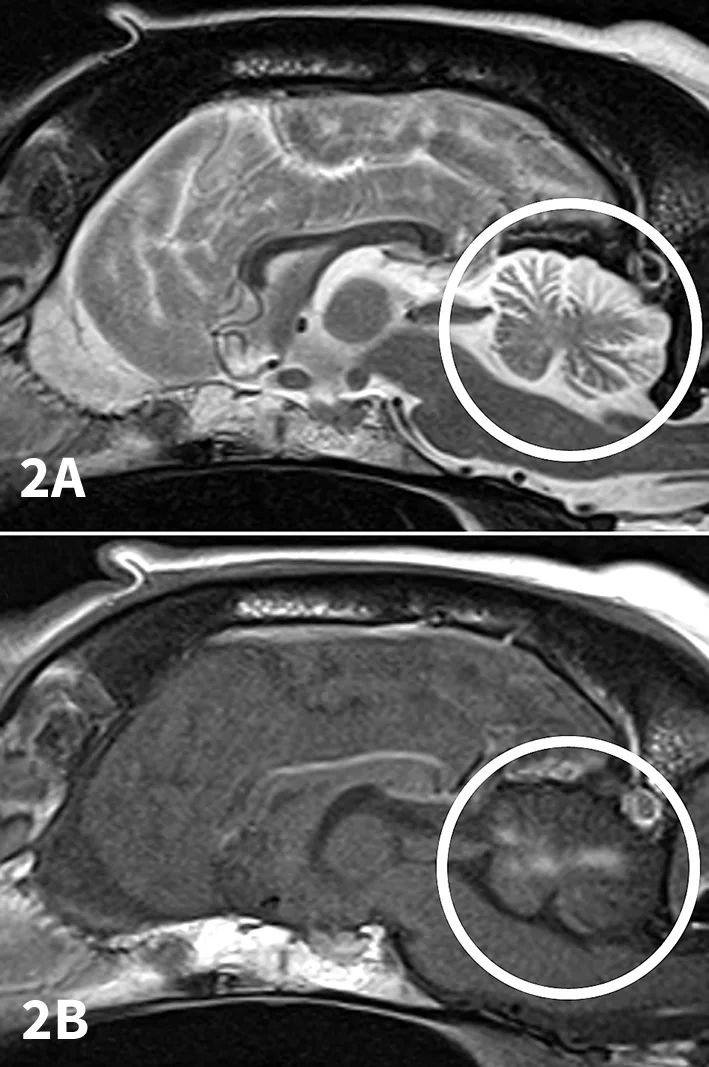

Figure 2

T2-weighted sagittal (A) and contrast-enhanced T1-weighted sagittal (B) MRI scans of a 6-year-old, spayed English springer spaniel dog with CNS neosporosis. The scans depict peripheral atrophy of the cerebellum (especially dorsally) with replacement by CSF (A and B). This finding is consistent with necrotizing cerebellitis. In addition, there is contrast enhancement of the cerebellar nuclei (B). The cerebellum is circled; compare to Figure 1.

MRI disclosed multiple intra-axial contrast-enhancing lesions with a generalized random distribution throughout the brain with specific involvement of the cerebellar nuclei, peripheral cerebellar atrophy with replacement by CSF (Figures 1 and 2). MRI also revealed bilateral temporal myopathy, which had not been present upon initial physical examination.